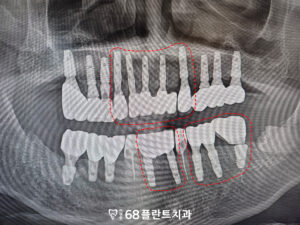

아래 송곳니는 발치 없이

신경치료와 크라운으로

보존할 수 있다고 진단을 내렸습니다.

먼저 치아를 발치 후

임플란트를 식립 하였습니다.

이후 임플란트가 뼈에 잘 달라붙고

치유가 되어,

보철 작업을 시작하였습니다.

그리고 기존 임플란트의 보철을 모두 제거한 후,

전체적으로 함께 보철물을

새롭게 제작하여

임플란트와 송곳니의 조화로운 기능과

미소를 완성하였습니다.

형태와 색상을 모두 자연스럽게 맞추어,

환자분과 함께 상의 후

영구접착을 진행하였습니다.

이로 인해, 자연스럽고

균형 잡힌 결과를

얻을 수 있었습니다.

◆ 전 > 후 ◆

전체적인 치료가 마무리된 후,

환자분께서는 치주질환으로 인해

안 좋았던 치아들을 발치하고

회복할 수 있어

매우 만족해주셨습니다.